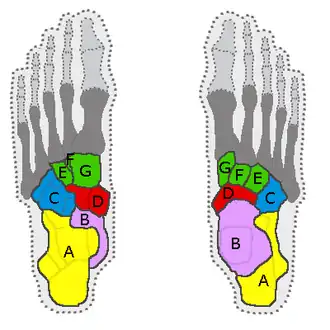

| Medial view, bones of the foot, navicular in green | |